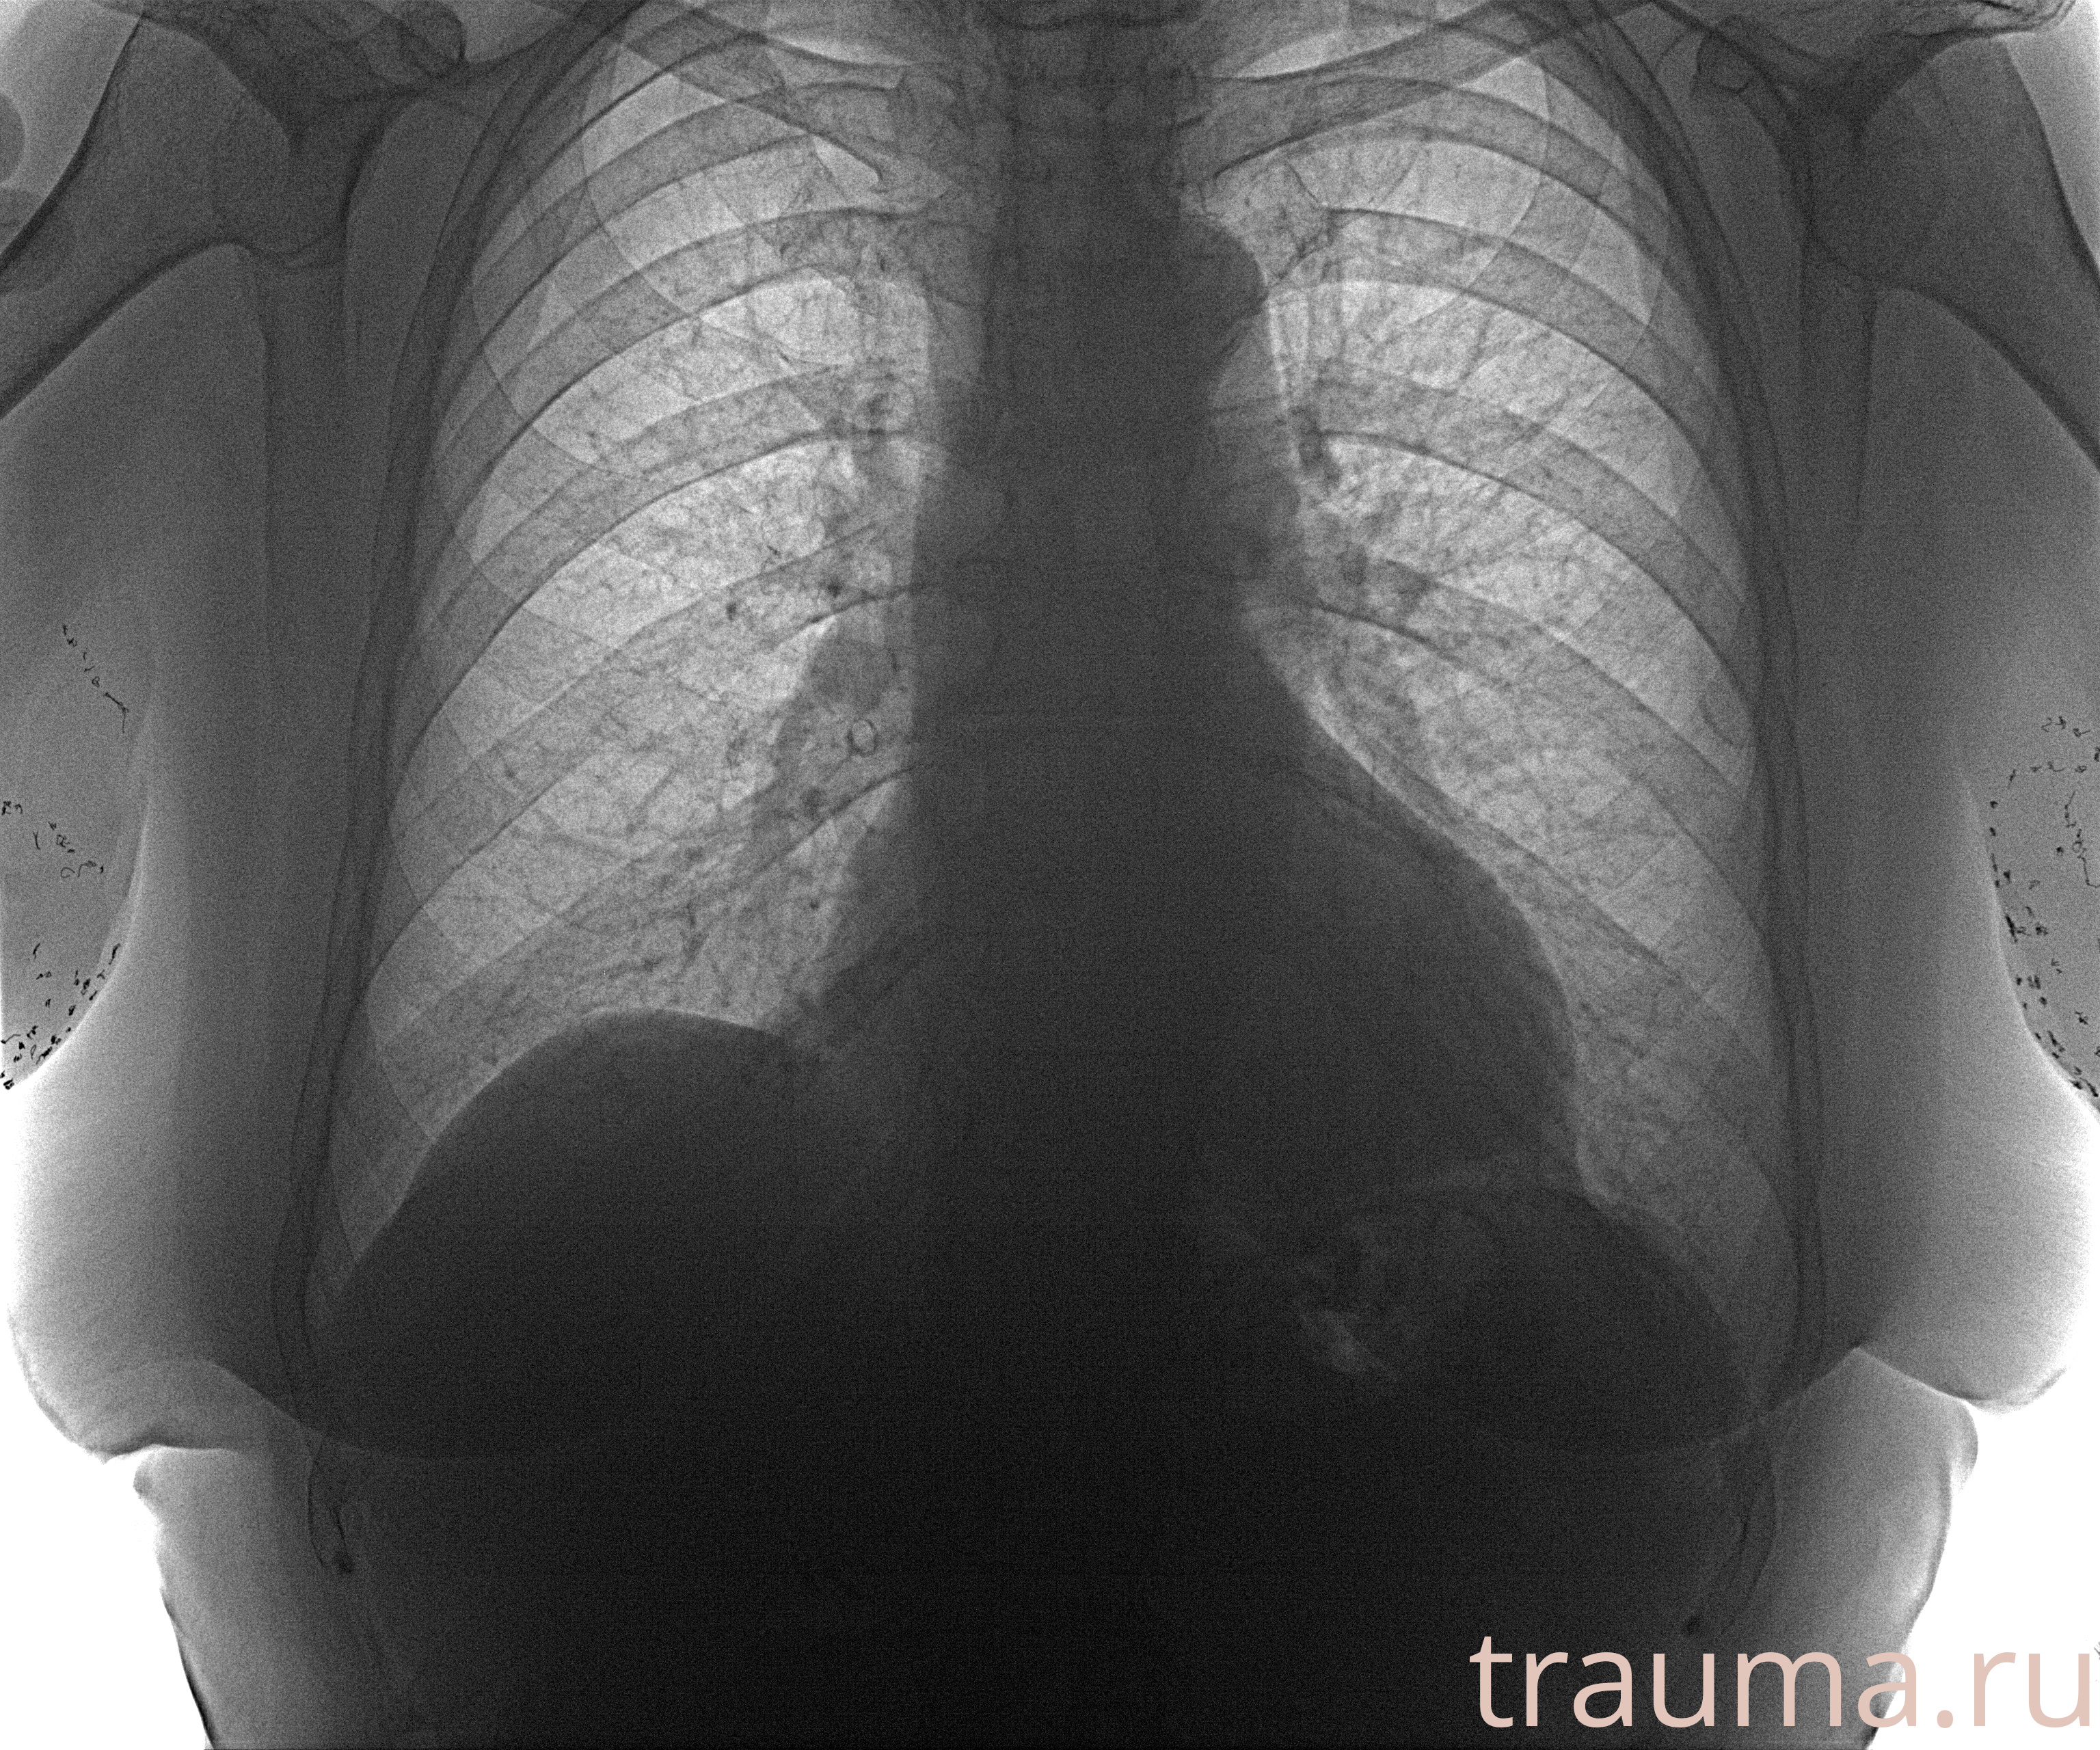

Рентген на дому: по вашему адресу приезжает врач-рентгенолог, травматолог-ортопед с мобильным рентгеновским аппаратом, проводит диагностику травмы или заболевания, делает необходимые рентгенограммы, дает рекомендации по дальнейшему лечению. Получить качественные снимки в домашних условиях возможно благодаря уникальной методике, разработанной МосРентген Центром для института  Склифосовского

при переломе шейки бедра и пневмонии от компании МосРентген Центр - партнера Института имени Склифосовского